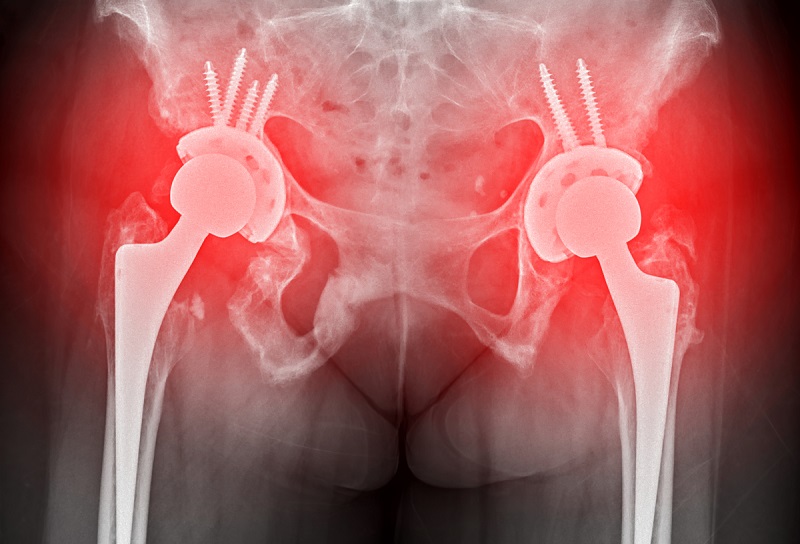

然而,如果骨折严重,如开放性骨折或关节不稳定、有错位或畸形等问题,就需要及时进行手术治疗了。手术方法可能包括切开复位术,即将股骨头在髋臼内得到同心圆坐落,以恢复正常功能;或者是髋关节置换术,用于缓解关节疼痛、矫正畸形、恢复和改善关节的运动功能。